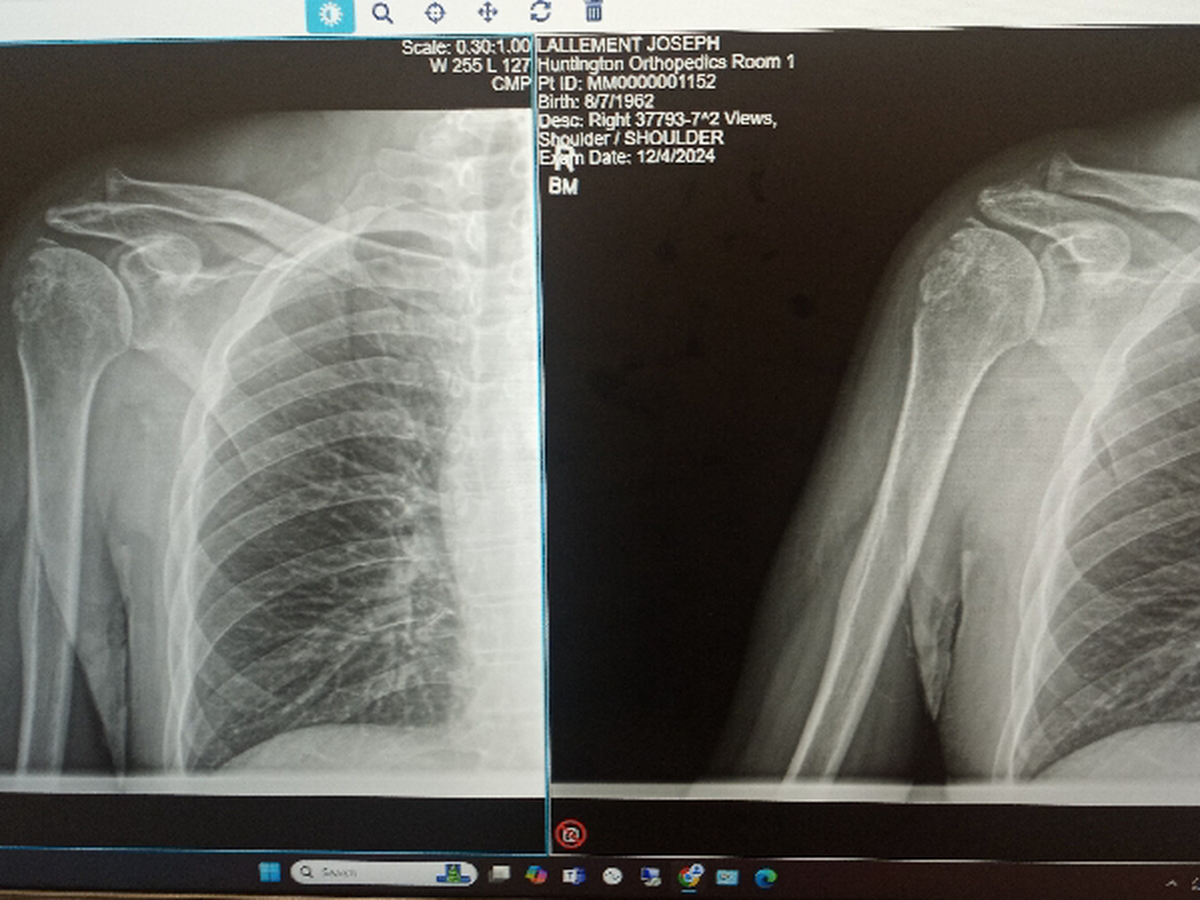

X-rays revealed that I had a fracture in the ball and another in the socket, as well a dislocation. Doctors made several attempts to reposition my shoulder, but the fractures complicated matters. Fortunately, at 4PM on October 5th, the doctors were able to reposition it while I was under general anesthetic and I didn't have to have surgery.

I am grateful to the doctors and staff at Huntington Hospital Pasadena for putting me back together without surgery, because at my age, recovery time would be so much longer and more difficult.